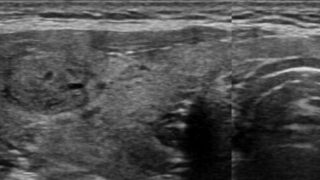

【症例】甲状腺髄様癌について悩む

お疲れ様です。先日精査で紹介した施設さんからのお返事を整理していました。地域柄か病理結果など丁寧に送っていただくことができます。ありがたいですね。大体は良性なのですが、たまに「手術しました」との内容もあります。今回は甲状腺の症例を書かせてい...